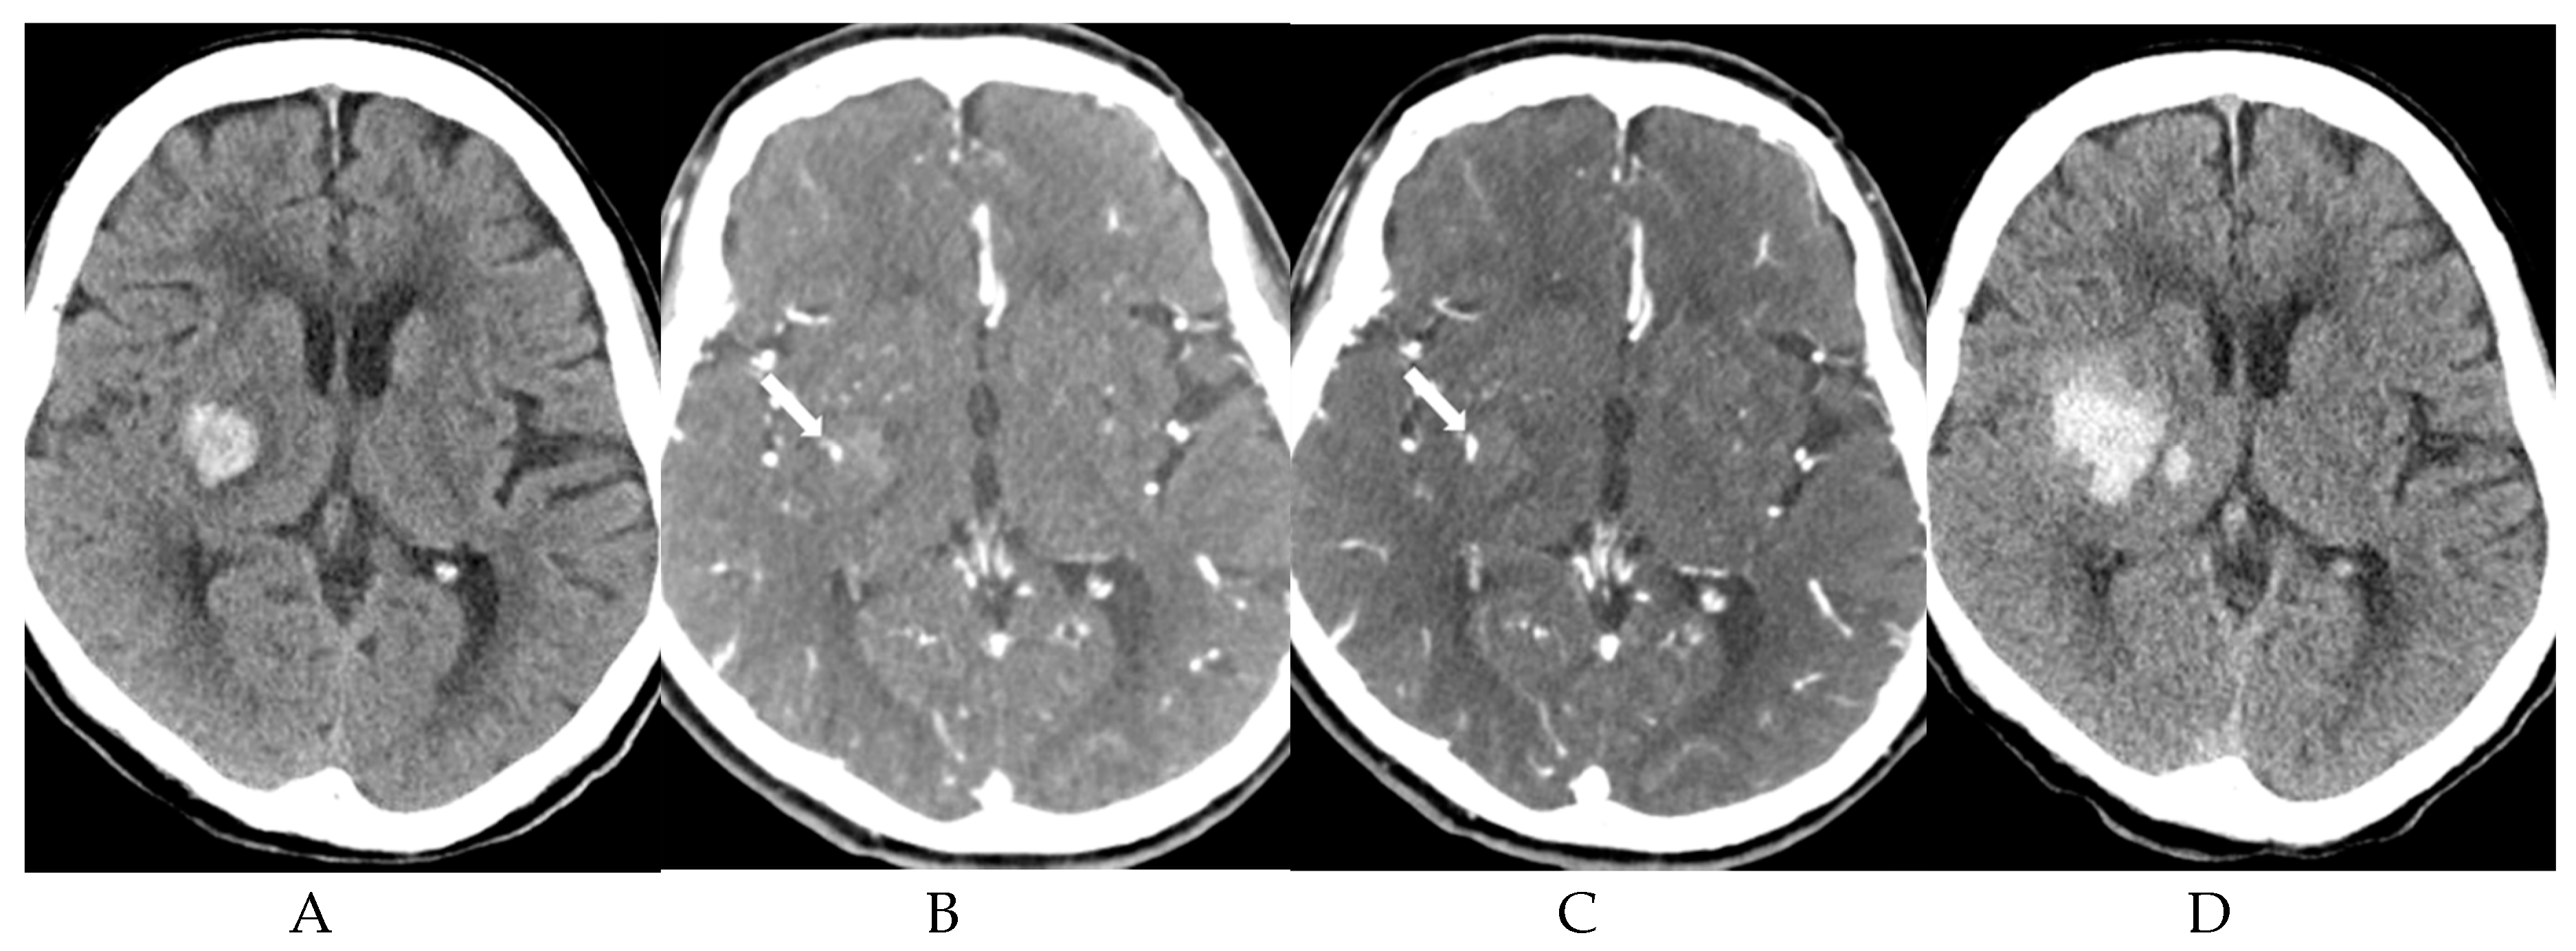

- Park, B.K.; Kwak, H.S.; Chung, G.H.; Hwang, S.B. Diagnostic value of swirl sign on noncontrast computed tomography and spot sign on computed tomographic angiography to predict intracranial hemorrhage expansion. Clin. Neurol. Neurosurg. 2019, 182, 130–135. [Google Scholar] [CrossRef]

- Rodriguez-Luna, D.; Coscojuela, P.; Rodriguez-Villatoro, N.; Juega, J.M.; Boned, S.; Muchada, M.; Pagola, J.; Rubiera, M.; Ribo, M.; Tomasello, A.; et al. Multiphase CT Angiography Improves Prediction of Intracerebral Hemorrhage Expansion. Radiology 2017, 285, 932–940. [Google Scholar] [CrossRef] [PubMed]

| Spot Sign | ICH Expansion (n = 26) | No ICH Expansion (n = 20) | p |

| First phase visualization | 25 (96.2) | 10 (50.0) | <0.001 |

| Increased size on second phase | 25 (96.2) | 10 (50.0) | <0.001 |

| First visualization on second phase | 1 (3.8) | 10 (50.0) | <0.001 |

| Linear pattern | 14 (53.8) | 9 (45.0) | 0.675 |

| Dot-like pattern | 12 (52.6) | 11 (55.0) | 0.675 |